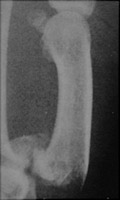

The Rolando fracture is really a fracture-dislocation of the base of the first metacarpal. The fracture is intraarticular and comminuted, distinguishing it from the noncomminuted Bennett fracture. There are usually three main fracture fragments.

- Click on the image for a larger versionAAP radiograph of the first digit. This demonstrates the comminuted intraarticular fracture at the base of the first metacarpal, a Rolando fracture.